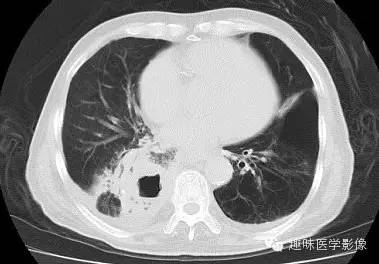

双肺多发无壁低密度区,以右肺下叶底部为主。右肺下叶见大片不规则实变阴影伴多发空洞影,实变肺组织内见支气管气象,右肺下叶支气管局部显示不清。纵隔内见淋巴结。右侧胸腔内见积液影,邻近胸膜肥厚。主动脉、冠状动脉钙化。

右肺下叶肺脓肿、肺炎伴胸腔积液,肺气肿、肺大泡。

右胸廓变小,心影右移;右肺下叶多房性空洞,空洞内未见明显液平面,右下肺病变应该是下叶阻塞性肺炎,实变肺组织内见支气管气像,邻近胸膜增厚,并合并胸腔积液,支持肺脓肿。